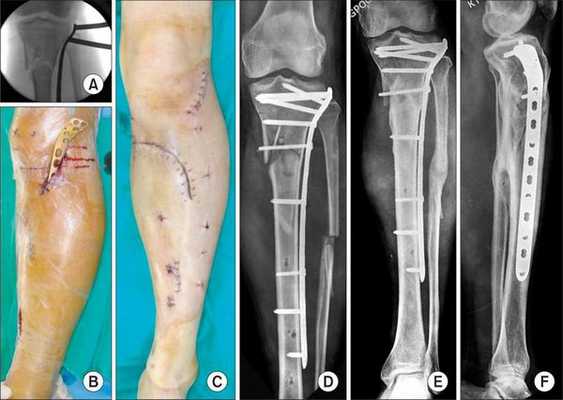

Хирургическое лечение состоит в открытой репозиции костных фрагментов и остеосинтезе — операции, при которой восстанавливают правильную ось ноги и придают отломкам нужное положение. Процедура проводится под общей анестезией. Подходящую технику остеосинтеза врач подбирает в зависимости от участка перелома.

При использовании металлоконструкций кости голени сращиваются в среднем через 3-3,5 месяца после операции. Удалять конструкции по медицинским показаниям можно не ранее, чем через полгода. К таким показаниям относятся риск перфорации кожи и травмы мягких тканей. Также конструкцию нужно убрать, если она мешает разработке сустава, сдвинулась или поломалась.

Если конструкция мешает пациенту, её можно удалить, но не раньше, чем через год.

Аппараты внешней фиксации, например стержневые фиксаторы или аппарат Илизарова, применяют только временно, пока состояние пациента нестабильно и нельзя провести операцию.